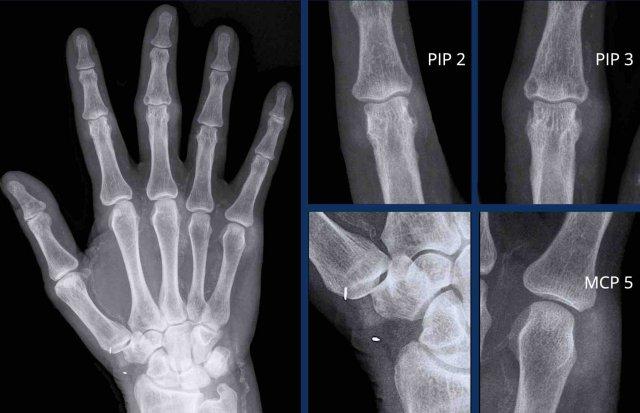

A

Tổn thương ăn mòn tại các khớp PIP 2-5 và DIP 3-5.

Biến dạng cánh hải âu điển hình tại DIP 3 (mũi tên trắng).

Dính khớp PIP 4 (mũi tên vàng), xuất hiện ở giai đoạn muộn của bệnh.

B

Hẹp khe khớp kèm ăn mòn trung tâm. Biến dạng cánh hải âu tại PIP 2-4, DIP 2 và khớp CMC-1.

Dính khớp DIP 3. Lệch trục về phía trong của PIP 2.